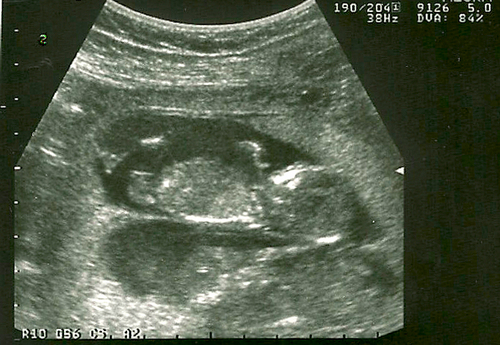

Les tannantes alors qu’elles étaient toujours confortablement installées dans le bedon de maman!

Elles devaient être trop bien pour ne pas être pressées de la sorte à venir au monde!